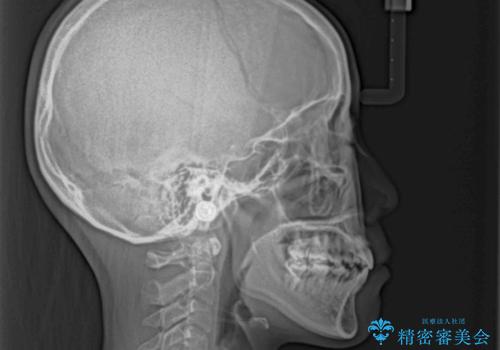

唇からはみ出るほど飛び出した前歯 ワイヤー装置による抜歯矯正

- 飛び出した上顎の前歯と八重歯を気にして来院された患者様です。

口元を積極的に引っ込めるために、上下左右の小臼歯計4本を抜歯することとしました。

舌の突出癖が強いため、しっかりと口元を引っ込めるため、舌のトレーニングをしっかりと行いながら矯正治療を行うこととしました。